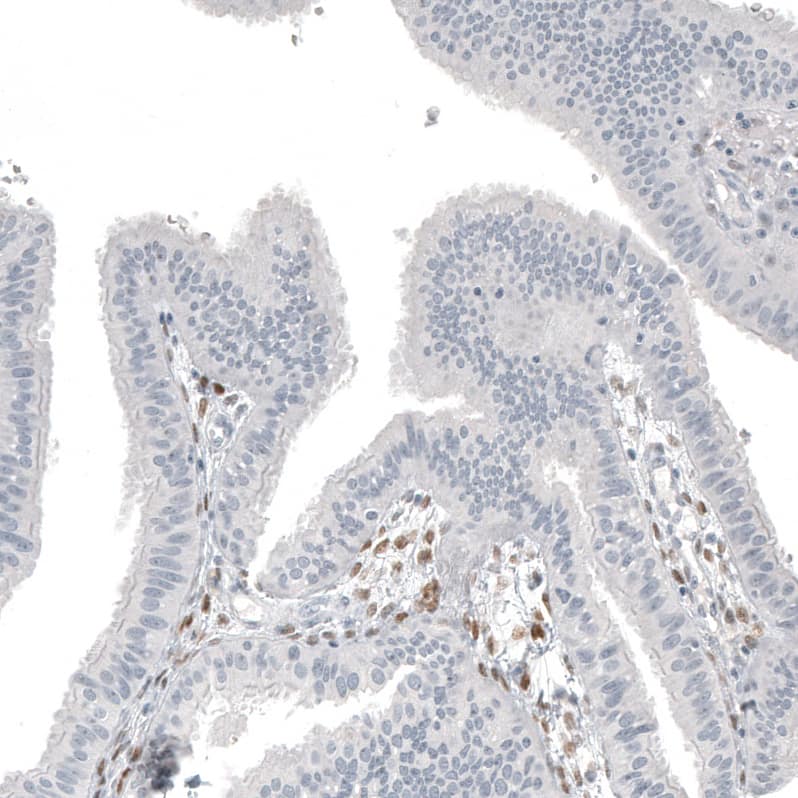

Staining of human ovarian cancer (sex cord tumor) shows strong nuclear positivity in tumor cells.